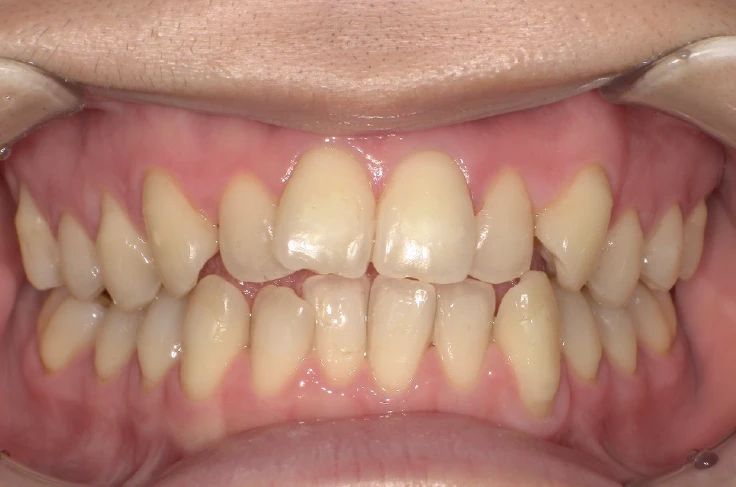

症例2

before

after

| 主 訴 | 着色を落としたい |

| 治療期間 | 通院 1回 |

| 治 療 費 | 1回 7,700〜11,000円(税込) |

| 治療内容 | PMTC |

| 治療のリスク | 歯自体の色を白くすることはできない。 しばらくすると再び着色することがある。 |